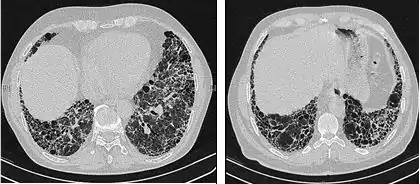

Chest X-rays are useful in the follow-up routine of IPF patients. Plain chest X-rays are unfortunately not diagnostic but may reveal decreased lung volumes, typically with prominent reticular interstitial markings near the lung bases.[3]

The radiological evaluation through HRCT is an essential point in the diagnostic pathway in IPF. HRCT is performed using a conventional computed axial tomographic scanner without injection of contrast agents. Evaluation slices are very thin, 1–2 mm.

Typical HRCT of the chest of IPF demonstrates fibrotic changes in both lungs, with a predilection for the bases and the periphery. According to the joint ATS/ERS/JRS/ALAT 2011 guidelines, HRCT is an essential component of the diagnostic pathway in IPF which can identify UIP by the presence of:[3]

- Reticular opacities, often associated with traction bronchiectasis

- Honeycombing manifested as cluster cystic airspaces, typically of comparable diameters (3–10 mm) but occasionally large. Usually sub-pleural and characterized by well-defined walls and disposed in at least two lines. Generally one line of cysts is not sufficient to define honeycombing

- Ground-glass opacities are common but less extensive than the reticulation

- Distribution characteristically basal and peripheral though often patchy.